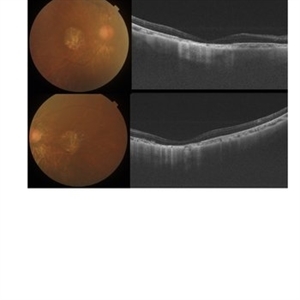

Fundus photograph of a 21-year-old male having complaints of blurring of vision. Had a viral prodrome 2 weeks before the onset of symptoms.

Imaging device: DRI OCT-1 Triton (plus) TOPCON

Condition/keywords: acute multifocal placoid pigment epitheliopathy (AMPPE)